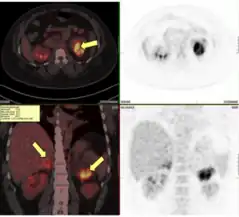

Fluorodeoxyglucose Positron emission tomographyCT scan shows enlarged adrenals with masses. Genetic and biochemical workup was consistent with congenital adrenal hyperplasia due to 21-hydroxylase deficiency.

A common finding in children experiencing an adrenal crisis is hypoglycemia. This could be linked to seizures, which are extremely dangerous and can result in permanent brain damage or even death.[70] Due to issues with adrenomedullary development as well as epinephrine production, hypoglycemia, and hemodynamic disturbance may be more prominent in the context of acute adrenal insufficiency in congenital conditions, including congenital adrenal hyperplasia, compared to other forms of primary adrenal insufficiency.[71] The severity of the enzyme impairment is correlated with the degree of adrenomedullary dysfunction.[72] Severe hyperkalemia has also been linked to potentially fatal cardiac arrhythmias.[73] Because the renal tubules' function is still developing in infants and early children with primary adrenal insufficiency, hyponatremia is of particular concern.[71]